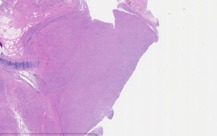

As part of the patient’s treatment, the thoracic surgery team performed a right middle and lower lobectomy. A 4-cm mass in the right bronchus intermedius without invasion into the lung parenchyma was revealed, and pathology confirmed the diagnosis of leiomyosarcoma. The sections of pulmonary tissue from the right middle and lower lobectomy showed a spindle cell tumor most consistent with leiomyosarcoma (Figure 3a-d). Most of the tumor was low grade, with some foci showing high-grade nuclear atypia and increased mitotic activity. Despite these rare mitotic figures, there was no evidence of necrosis. Following surgery, chemotherapy was planned for the patient. However, the patient’s postoperative course was complicated by persistent hypoxic respiratory failure, hypovolemic and hemorrhagic shock, and acute kidney injury. Her respiratory status continued to decline, and she went into cardiac arrest with pulseless electrical activity. She was resuscitated; however, her shock and respiratory failure worsened despite aggressive therapy. Her family chose to transition her to comfort care, and the patient died.